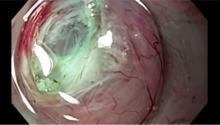

A newer option, available in specialized centers, is peroral endoscopic myotomy (POEM). POEM is a totally endoscopic procedure, utilizing the advanced endoscopic technique of submucosal tunneling. Once positioned well above the UES (upper esophageal sphincter), a submucosal fluid cushion is created and an incision is made with an endoscopic knife (Figure 1 [3]). The scope is advanced into the submucosal layer of the esophagus (Figure 2 [4]). Using water jet injection, suction, low-dose energy ablation, and blunt dissection, the scope is advanced past the esophago-gastric junction in the submucosal plane (Figure 3 [5]). Either a myotomy limited to the circular muscle (Figure 4 [6]) or a full thickness myotomy (Figure 5 [7]) is then performed. The mucosal incision is then closed with hemostatic clips (Figure 6 [8]).